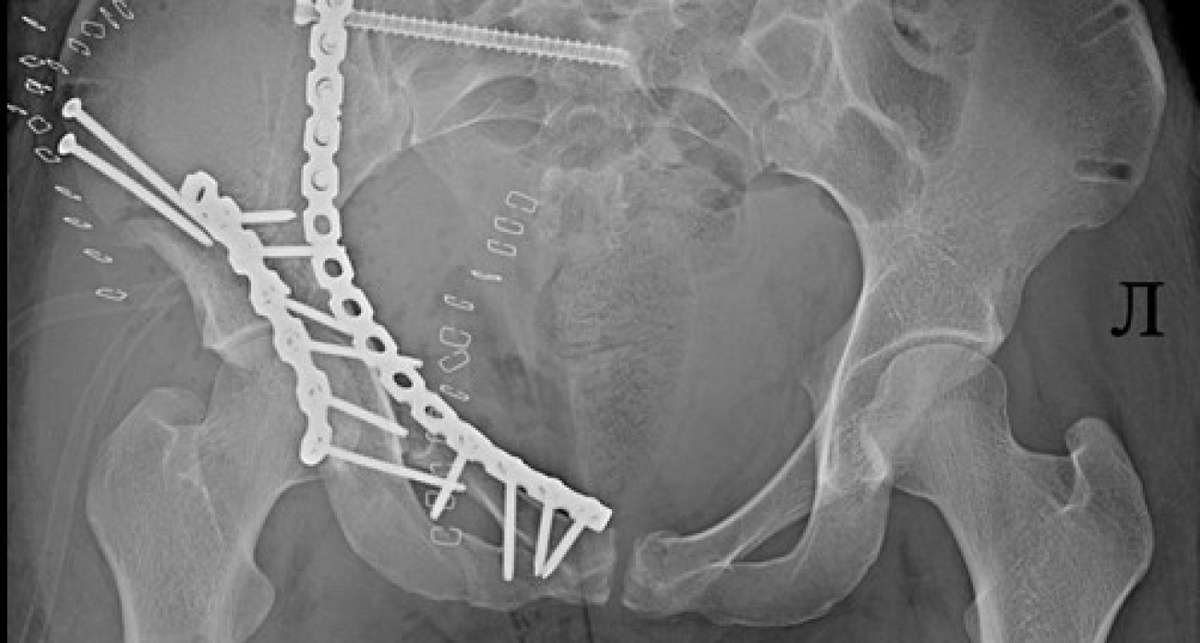

В Ярославле 25-летняя девушка оказалась в реанимации после удара о бетонный блок на стихийной горке. У нее — множественные переломы таза и впереди долгие месяцы реабилитации.

За первые две недели новогодних каникул в больницу Соловьева поступили пятеро пострадавших. Травмы, полученные при катании на тюбинге, сравнимы с последствиями столкновения автомобилей на скорости около 60-80 км/ч.

"Лечение таких повреждений чрезвычайно сложное и длительное. Оно включает многоэтапные операции, иногда продолжительностью пять часов, использование наружных фиксаторов и имплантатов, длительный период восстановления",-рассказали в больнице.